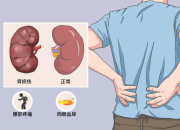

对于肾脏,大家可能是既熟悉又陌生,它是人体的重要器官,负责过滤血液中的废物、调节水分和电解质平衡、维持血压和产生红细胞等。慢性肾病(CKD)是全球重要的公共卫生问题,影响超过8.5亿人,数据表明,预计到2040年,慢性肾病将成为全球导致预期寿命缩短的第五大病因。慢性肾病早期往往没有明显症状,因此容易被忽视,当肾脏功能严重受损时,可能会导致肾衰竭,甚至需要透析或肾移植来维持生命。根据中国医师协会肾脏